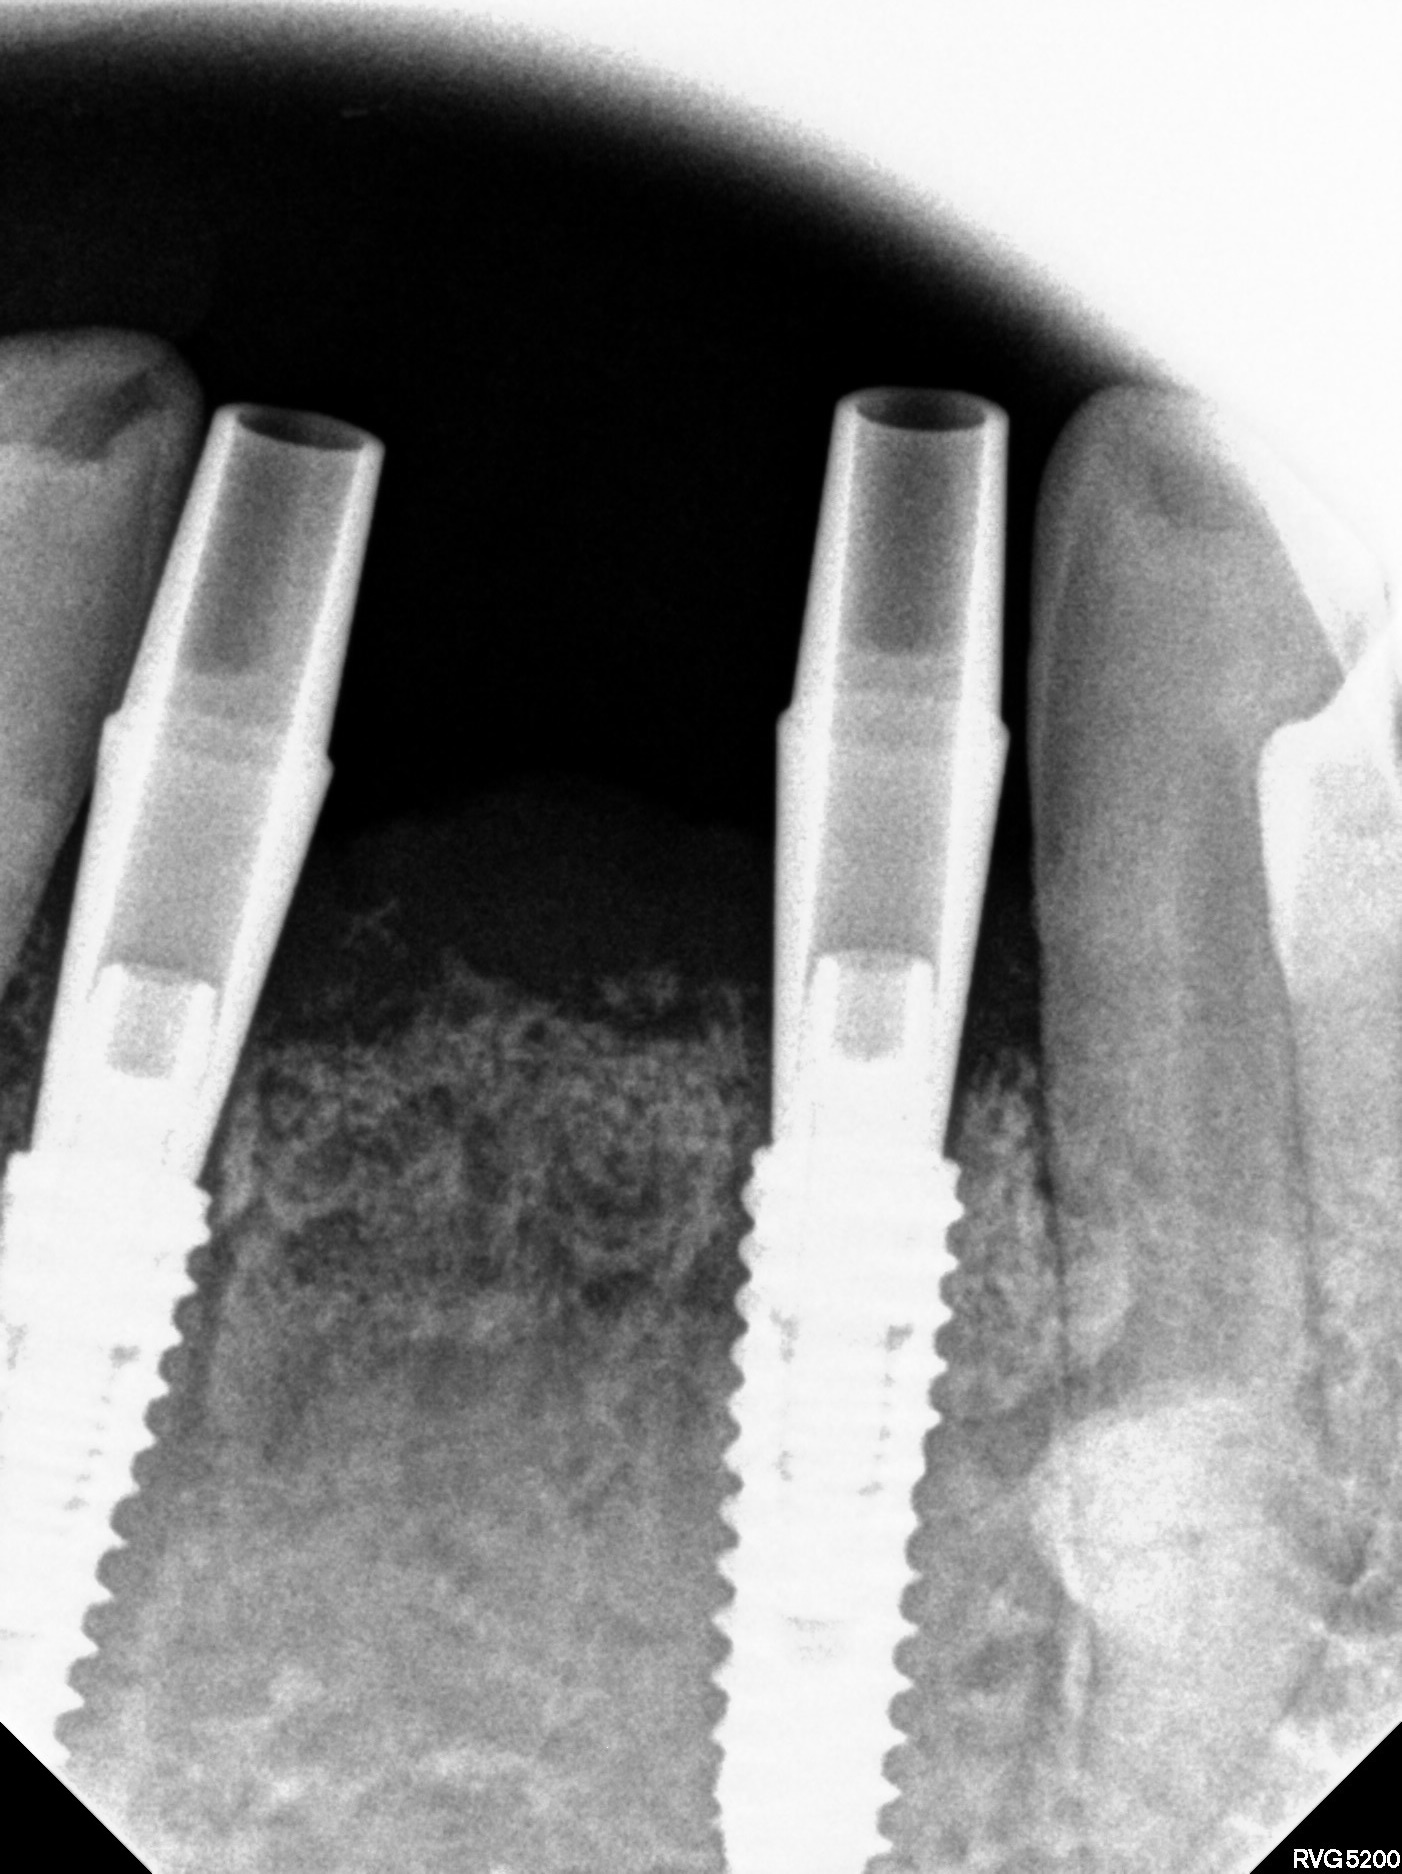

임플란트 식립위치 결정

• STEP 04

네비게이션 가이드 제작

CT와 구강스캔 데이터를 결합해 수술 전 3D 시뮬레이션으로 식립 위치·각도·깊이를 정밀 계획합니다.